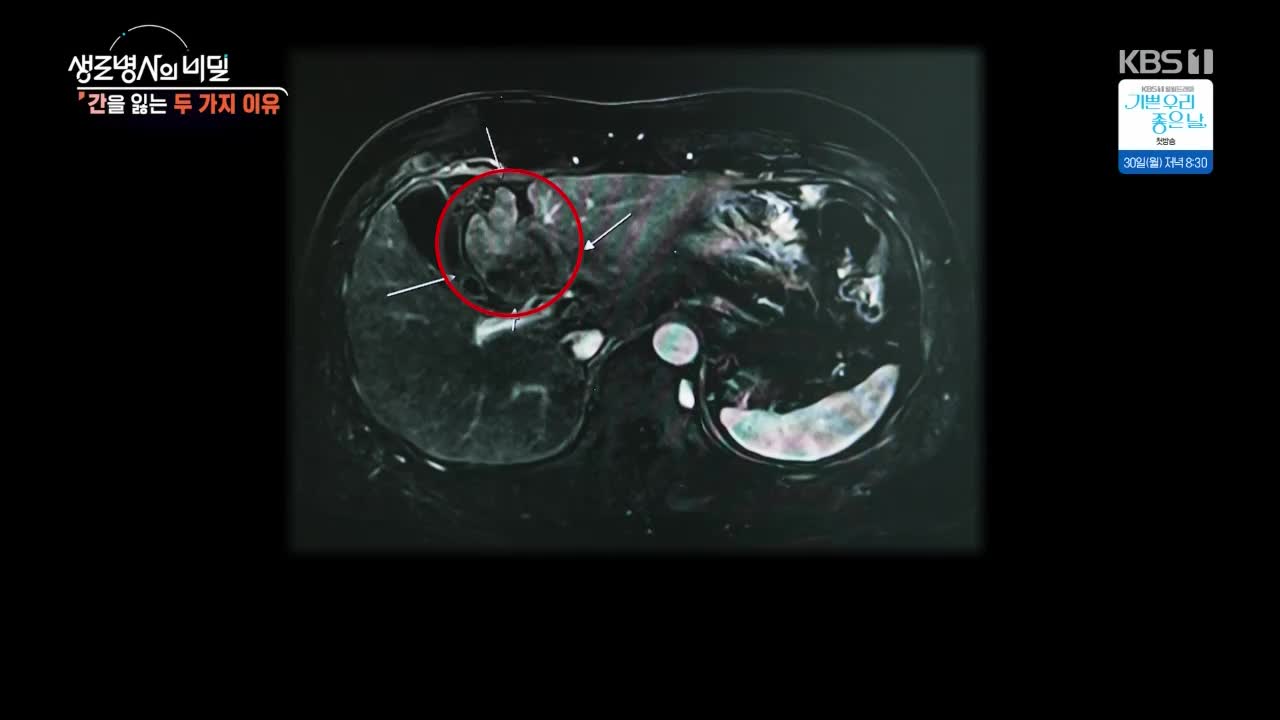

먹고, 자고, 활동하는 우리 삶에 대한 총체적인 접근을 통해 ‘건강지수’와 ‘행복지수’를 동시에 높일 수 있는 ‘건강한 삶의 방식’을 제시하는 프로그램